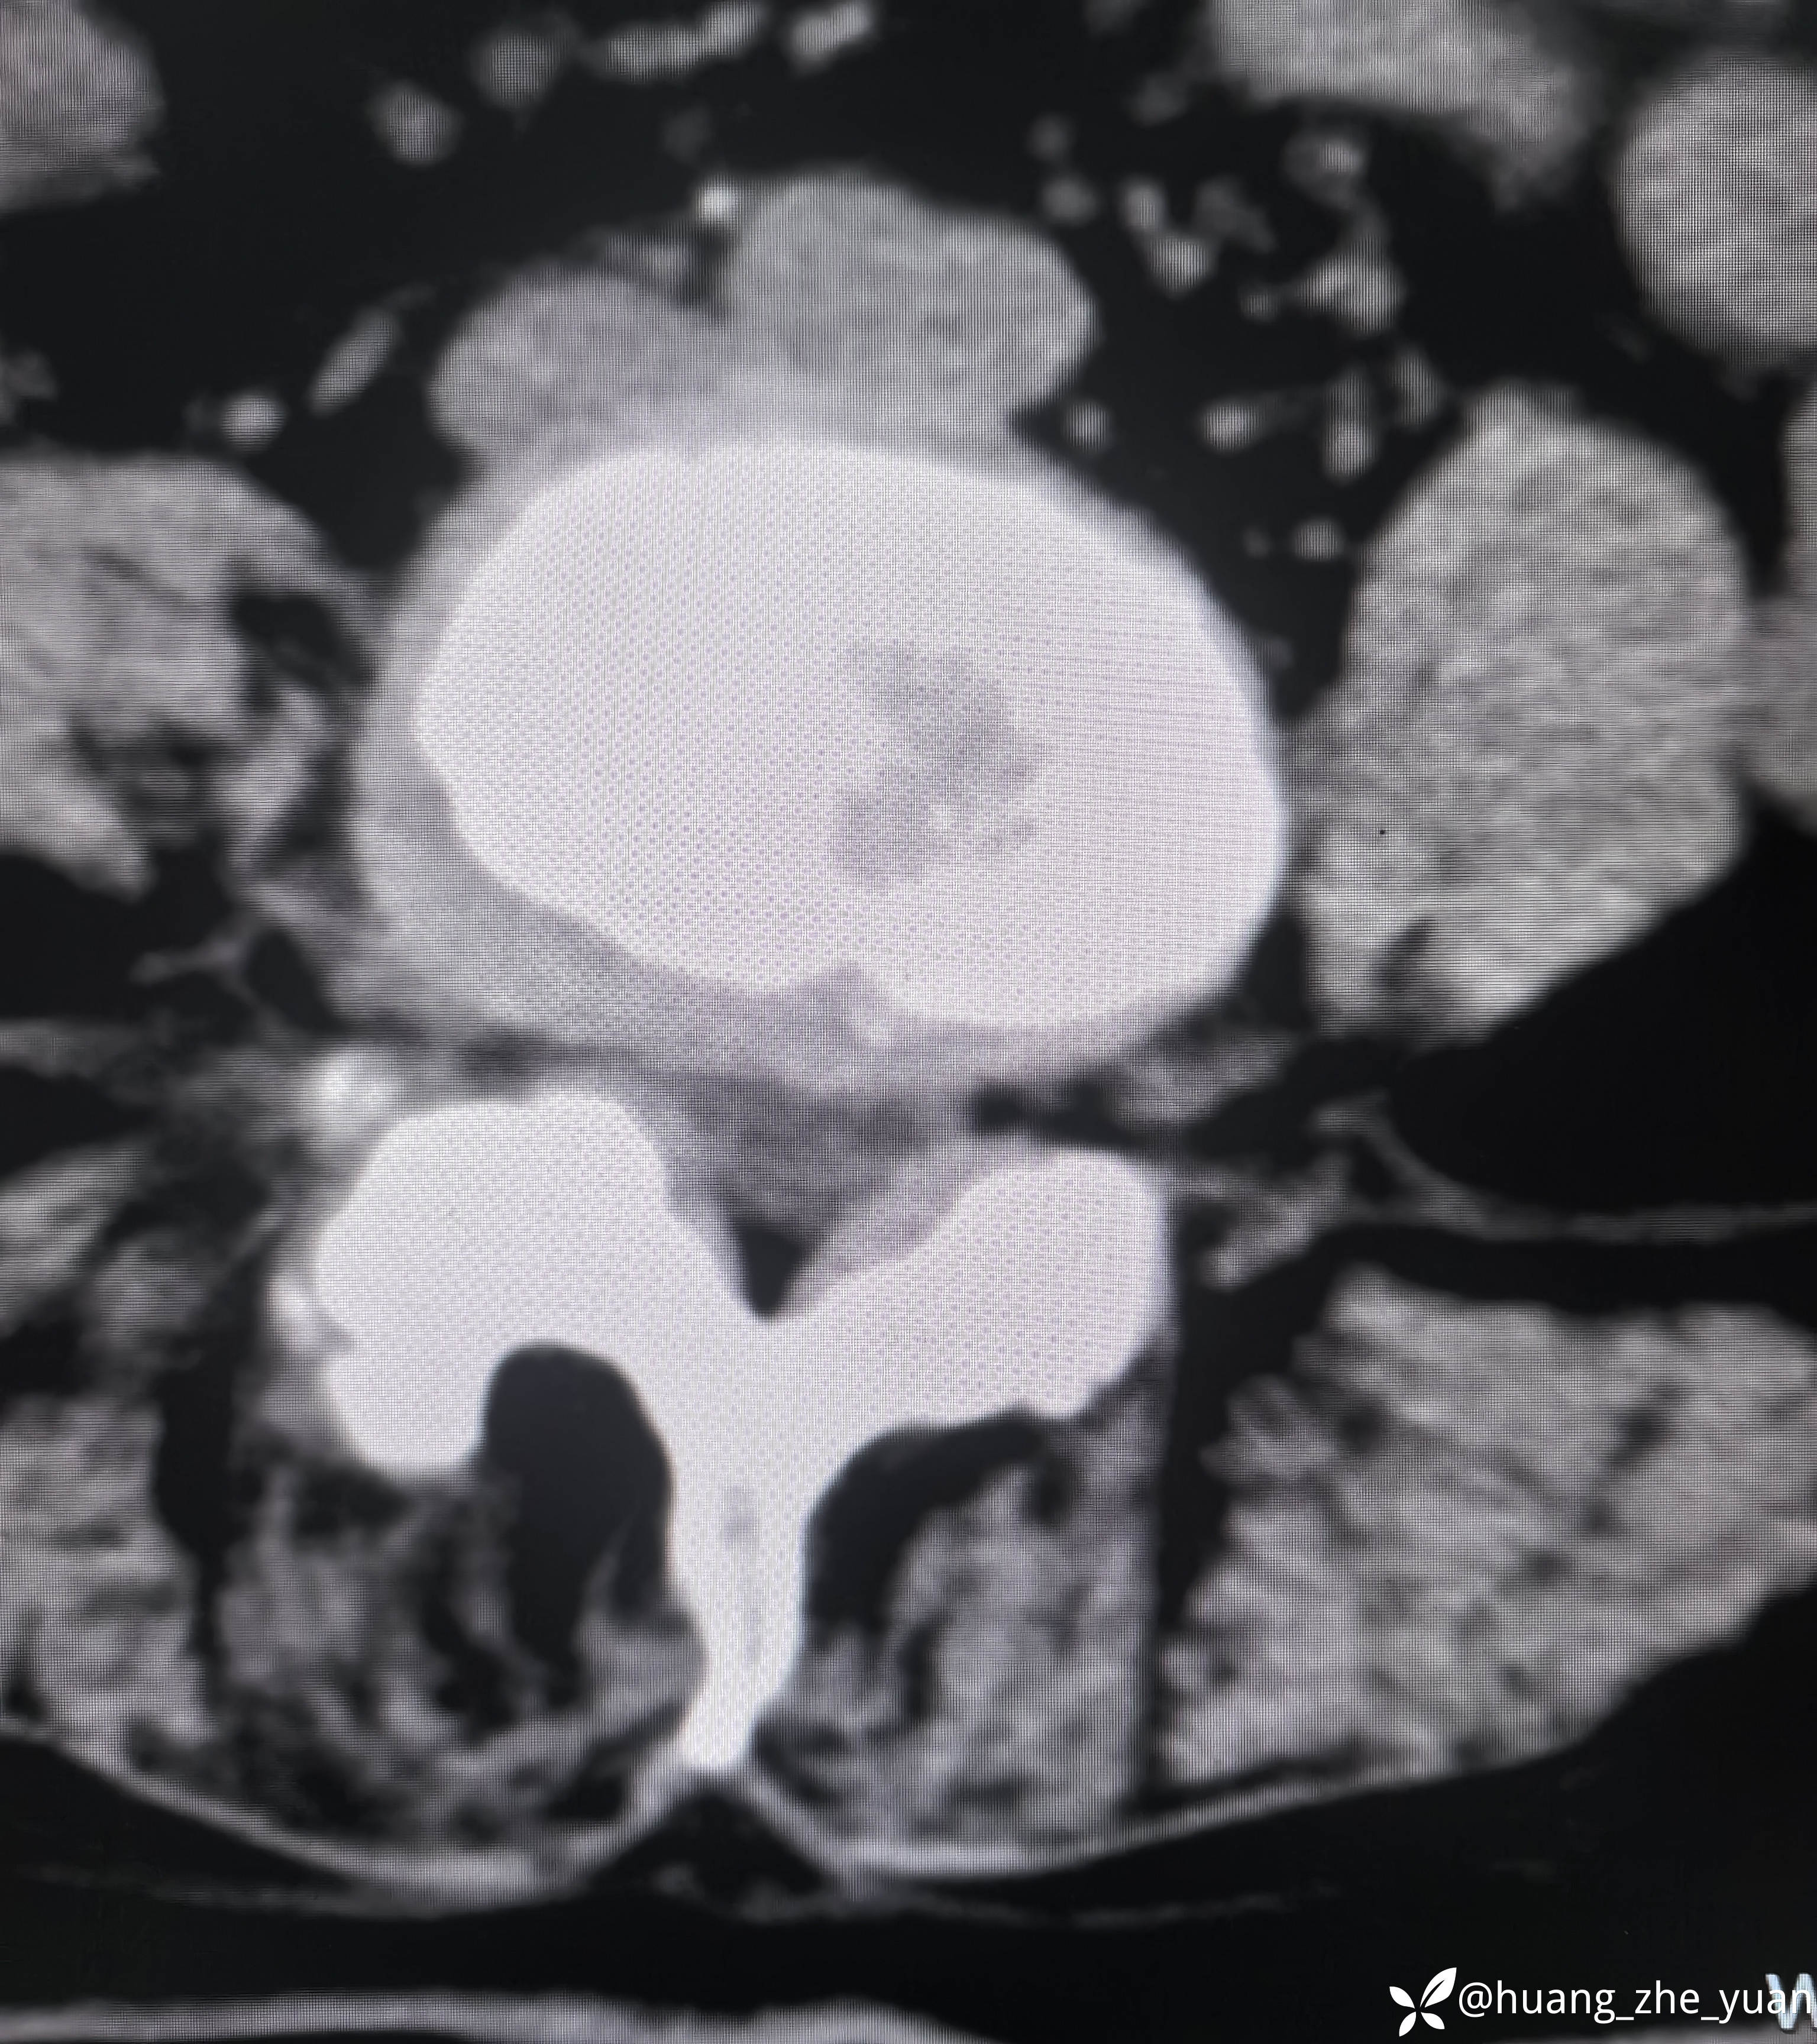

70岁女性,反复右下肢放射痛八个月。合并症:糖尿病,胰岛素泵控制。